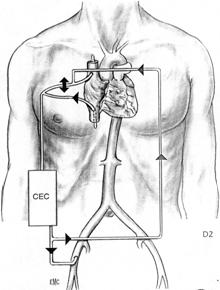

1) Arresto di circolo in ipotermia profonda

Il paziente viene posto in circolazione extracorporea ( CEC ) dopo avere incannulato l'arteria femorale e l'atrio destro, mediante due cannule o una singola ( two stage ) cannula e la sua temperatura corporea abbassata progressivamente a 15-18 °C. A questa temperatura la CEC viene fermata ed il sangue del paziente raccolto dentro l'ossigenatore ed il cardiotomo, in modo da rendere il campo chirurgico esangue. La protezione cerebrale viene migliorata apponendo alcuni sacchetti di ghiaccio attorno alla testa del paziente, che è stato preventivamente posizionato in Trendelemburg. L'ipotermia profonda, riducendo l'attività metabolica cellulare, consente l'arresto di circolo per un intervallo di tempo cosiddetto "sicuro", in cui le cellule, utilizzando le riserve d'energia disponibili, non vanno incontro ad alterazioni irreversibili e riprendono la loro normale funzione dopo il ripristino della normotermia.

Il periodo sicuro è influenzato da diversi fattori quali: la velocità di raffreddamento, la temperatura cerebrale media, la pressione arteriosa, il livello di catecolamine, il grado di ipotermia. Studi recenti indicano che se l'ipotermia è dell'ordine di 15-18°C il periodo "sicuro" ha la durata di circa 45 minuti e che i livelli di ATP si riducono del 65%. E' stato dimostrato che tra i 45 e i 60 minuti, il rischio di danni cerebrali irreversibili è del 65% e che oltre i 60 minuti il danno cerebrale interessa il 100% dei casi.

2) Ipotermia profonda, CEC e perfusione cerebrale retrograda

Questa tecnica prevede l'inversione del flusso ematico sulla linea venosa durante la fase di arresto di circolo. La CEC viene iniziata dopo avere incannulato le due vene cave e l'arteria femorale. Si raffredda progressivamente il paziente e non appena si raggiunge la temperatura di 15-18 °C si ferma la CEC e si inizia la perfusione retrograda della vena cava superiore collegata alla linea arteriosa, a bassi flussi, 500 - 800 ml/min/mq s.c., mantenendo una pressione cavale superiore compresa tra 20 e 25 mmHg. Il sangue refluo dal circolo cerebrale viene aspirato a livello dell'aorta ascendente.

Tale tecnica consente di prolungare oltre il limite dei 60 minuti il tempo di arresto di circolo.

3) Ipotermia profonda, CEC e perfusione anterograda

La caratteristica di questa tecnica è che durante la fase di arresto di circolo, viene eseguita la perfusione cerebrale anterograda continua, mediante la cannulazione selettiva ed il collegamento alla linea arteriosa della CEC, del tronco arterioso anonimo e della carotide comune sinistra.

4) Perfusione cerebrale selettiva anterograda secondo Kazui ( Selective Cerebral perfusion - SCP)

Dopo aver posto il paziente in circolazione extracorporea, la temperatura nasofaringea viene abbassata a valori di 22 - 25°C ( ipotermia moderata ) e la circolazione sistemica viene arrestata. Aperta l'aorta ascendente, con il paziente in posizione di Trendelemburg, si procede alla cannulazione sia del tronco anonimo che della carotide comune di sinistra utilizzando delle apposite cannule. La perfusione cerebrale selettiva è iniziata alla velocità di 10ml/Kg/min usando una apposita pompa roller indipendente dalla circolazione sistemica, mantenendo una pressione in arteria radiale destra tra 40 e 70 mmHg. Durante la SCP, l'arteria succlavia di sinistra generalmente viene clampata od occlusa utilizzando un catetere di Fogarty per evitare fenomeni di "furto" o un importante reflusso di sangue che potrebbe creare fastidi al chirurgo.

Studi sperimentali eseguiti da Kazui e coll. suggeriscono che per un'adeguata protezione cerebrale la velocità di perfusione cerebrale in ipotermia moderata deve essere almeno il 50% della perfusione fisiologica. Una velocità di perfusione di 10ml/kg/min, quale si effettua durante la SCP, è considerata essere il 50% o più della velocità di flusso fisiologica della circolazione cerebrale. Gli stessi studi hanno comparato l'efficacia della protezione cerebrale nel corso dell'ipotermia profonda con arresto di circolo, della perfusione cerebrale anterograda e della perfusione cerebrale selettiva anterograda, e da ciò é scaturito che il metodo più sicuro di protezione cerebrale, specie in interventi molto lunghi e complessi quali ad esempio la sostituzione dell'arco aortico, è rappresentato dalla perfusione cerebrale selettiva anterograda. Particolare attenzione, tuttavia, durante SCP deve essere posta all'introduzione e al posizionamento delle cannule, per prevenire eventuali dissezioni distali dei vasi epiaortici o il distacco di frammenti di placche aterosclerotiche, con gravi fenomeni di microembolizzazione cerebrale.

I problemi neurologici sono dunque le complicanze più importanti derivanti dalla sospensione della circolazione cerebrale durante gli interventi sull'aorta e per prevenire queste complicanze varie metodiche sono state ampiamente utilizzate. L'ipotermia profonda con arresto di circolo, utilizzata per la prima volta nel 1974 da Pierangeli e coll., è una metodica semplice e valida, tuttavia ha lo svantaggio di un limitato periodo di "sicurezza" durante la fase di arresto di circolo (45 min. a 18 °C). Con questa tecnica l'incidenza di complicanze cerebrali si aggira tra il 7 e il 10%. Tuttavia il periodo di CEC prolungato, necessario per raffreddare e riscaldare il paziente, accresce i rischi legati a deficit della coagulazione, complicanze polmonari e microembolismi.

La perfusione cerebrale retrograda associata all'arresto di circolo, introdotta per aumentare il periodo di sicurezza durante la fase di arresto di circolo, è una tecnica che ha dato buoni risultati, (Coselli e coll.) ma tuttavia non evita problemi associati all'arresto di circolo e all'ipotermia profonda.

Questa tecnica, utilizzando l'ipotermia moderata (22-25°C), riduce i problemi causati dall'ipotermia profonda, previene gli insulti ischemici dei visceri addominali e del midollo spinale ed inoltre ha considerevolmente prolungato il tempo di "sicurezza" durante la fase di arresto di circolo.